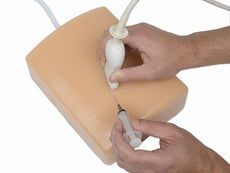

Midscapular Thoracentesis Ultrasound Training Model

The model is of a supine adult male and extends from the upper buttocks to the lower neck. Positioned in the mid scapulary line, the ultrasound tissue insert contains chest wall superficial tissue, 6th, 7th, 8th, and 9th ribs and intercostal spaces, pleural cavity with lung and atelectatic lung, diaphragm, and superior spleen. The pleural fluid collections allow users to develop and refine their ultrasound guided thoracentesis skills. This model is extremely realistic and is self-healing offering you superb training with a low cost of ownership.

The ultrasound tissue insert offers extremely realistic sonographic imaging characteristics is designed for guiding the placement of needles and small catheters (18-21 gauge and associated catheter kits). Blue Phantom simulated human tissue is very realistic and ultra-durable; excellent for repeated training in skills associated with ultrasound guided thoracentesis procedures. Positive fluid flow offers users feedback when pleural effusions are accurately accessed. The fluid is easily refilled using a quick fill luer lock or can be connected to an I.V. reservoir for continuous fluid delivery. Users can also learn to avoid accessory structures as the spleen, diaphragm and lung.

Blue Phantom's mid-scapular thoracentesis ultrasound training model is specifically designed for ultrasound guided thoracentesis procedures. This ultrasound training phantom aids users in developing and practicing the skills associated with a mid scapulary approach to ultrasound guided thoracentesis procedures. This model is excellent for assisting clinicians in gaining proficiency in using ultrasound to identify and guide needle and small gauge catheter insertions in a patient with pleural effusions for diagnostic and/or therapeutic purposes.The model is of a supine adult male and extends from the upper buttocks to the lower neck. Positioned in the mid scapulary line, the ultrasound tissue insert contains chest wall superficial tissue, 6th, 7th, 8th, and 9th ribs and intercostal spaces, pleural cavity with lung and atelectatic lung, diaphragm, and superior spleen. The pleural fluid collections allow users to develop and refine their ultrasound guided thoracentesis skills. This model is extremely realistic and is self-healing offering you superb training with a low cost of ownership.

The ultrasound tissue insert offers extremely realistic sonographic imaging characteristics is designed for guiding the placement of needles and small catheters (18-21 gauge and associated catheter kits). Blue Phantom simulated human tissue is very realistic and ultra-durable; excellent for repeated training in skills associated with ultrasound guided thoracentesis procedures. Positive fluid flow offers users feedback when pleural effusions are accurately accessed. The fluid is easily refilled using a quick fill luer lock or can be connected to an I.V. reservoir for continuous fluid delivery. Users can also learn to avoid accessory structures as the spleen, diaphragm and lung.